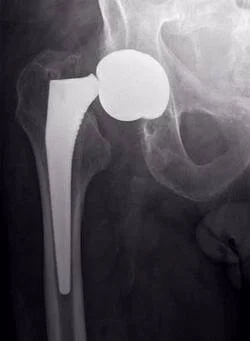

Как видно на приведенной рентгенограмме, после удаления эндопротеза остаётся "пустое место" в области бывшего тазобедренного сустава.

Это ведёт к децентрации головки эндопротеза (на представленной рентгенограмме видно смещение головки эндопротеза от центра) и нарушению функции конечности.